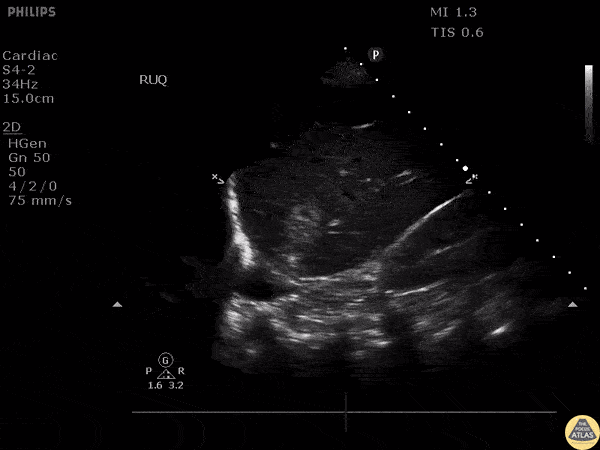

Bowel-GI - Liver Metastasis

Patient with history of colon cancer presented with right flank pain. RUQ scan revealed metastatic liver disease. Image courtesy of Robert Jones DO, FACEP @RJonesSonoEM Director, Emergency Ultrasound; MetroHealth Medical Center; Professor, Case Western Reserve Medical School, Cleveland, OH View his original post here